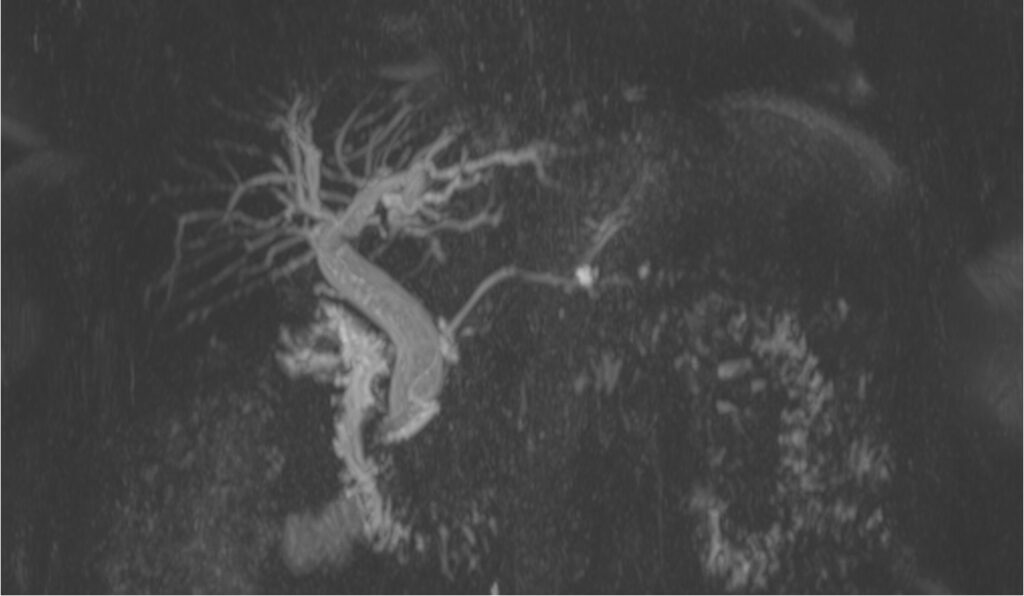

Colangio-RM

Cos’è? La Colangio-RM è un esame di risonanza magnetica dell’addome superiore che prevede l’esecuzione di sequenze specifiche mirate alla valutazione anatomica delle vie biliari intra